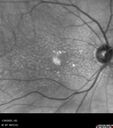

Conversion to Wet AMD after Izervay32 views83 year old man whose left eye had minimal GA and converted from dry to wet AMD after a single Izervay treatment

Conversion to Wet AMD after Izervay31 views83 year old man whose left eye had minimal GA and converted from dry to wet AMD after a single Izervay treatment

Conversion to Wet AMD after Izervay30 views83 year old man whose left eye had minimal GA and converted from dry to wet AMD after a single Izervay treatment

Conversion to Wet AMD after Izervay29 views83 year old man whose left eye had minimal GA and converted from dry to wet AMD after a single Izervay treatment

Conversion to Wet AMD after Izervay28 views83 year old man whose left eye had minimal GA and converted from dry to wet AMD after a single Izervay treatment

Conversion to Wet AMD after Izervay27 views83 year old man whose left eye had minimal GA and converted from dry to wet AMD after a single Izervay treatment

Conversion to Wet AMD after Izervay26 views83 year old man whose left eye had minimal GA and converted from dry to wet AMD after a single Izervay treatment

Conversion to Wet AMD after Izervay25 views83 year old man whose left eye had minimal GA and converted from dry to wet AMD after a single Izervay treatment

Conversion to Wet AMD after Izervay24 views83 year old man whose left eye had minimal GA and converted from dry to wet AMD after a single Izervay treatment